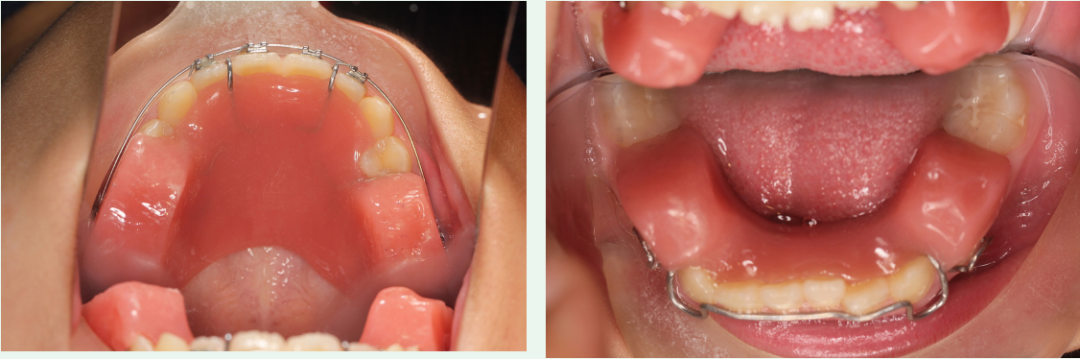

那么替牙期引导下颌向前的方法其实比较多,我们常用的有2x4口外弓、Twin Block、斜导工具、隐形牙套+II类颌间牵引、Activitor肌激动器、FrankelⅡ等。

如果让我来界定这几种功能矫治器使用的标准,我认为如果是个高角的病例,你还想引导下颌前伸,我觉得Twin Block应该是比较好的,毕竟后部有个树脂块,戴上的时候后部的颌间距离就会增加到大于4毫米以上,一旦你大于4毫米,整个这个面部肌肉就被拉伸了,拉伸的时候肌肉就会收缩。

所以肌肉一旦发现收缩的时候,就会通过这个颌板产生压缩的作用,对后牙会产生压低的效果,那高角当然后牙压低会好。

如果是均角或者是低角病例,我觉得常规的斜导就足够了,所以没有必要去做那种复杂的装置。